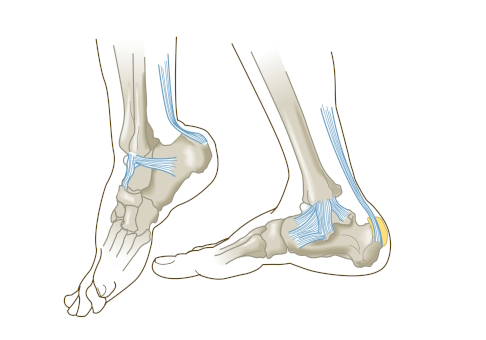

Schleimbeutelentzündung am Fuß oder an der Ferse

Am Fuß gibt es mehrere Schleimbeutel, die sich entzünden können. Dazu gehören die Schleimbeutel am oberen Ende des Fersenbeins (Bursa subcutanea calcanea und Bursa retrocalcaneale), die Schleimbeutel am Innen- und Außenknöchel (Bursa subcutanea malleoli medialis und lateralis), der Schleimbeutel am Großzehengrundgelenk (Bursa metatarsophalangealis) oder der Schleimbeutel unter der Fußsohle im Bereich des Vorfußes (Bursa metatarsale).

Unterschiedliche Erkrankungen im Bereich des Fußes und Sprunggelenks können die verschiedenen Schleimbeutel reizen und zu Fußschmerzen oder Fersenschmerzen führen. So kommt es häufig beim Hallux valgus (Ballenzeh) zur Reizung und Entzündung des Schleimbeutels am Großzehengrundgelenk. Ist ein Schleimbeutel im Bereich der Ferse betroffen (Achillobursitis), liegt oftmals eine Haglundferse vor. Durch das Reiben am Schuh treten teils heftige Schmerzen auf. Oftmals ist schmerzfreies Gehen oder Sport nicht mehr möglich.

In vielen Fällen ist auch eine Überlastung oder Dauerreizung ursächlich für die Schleimbeutelentzündung am Fuß. Betroffen sind vor allem Läufer. Auch unpassendes Schuhwerk kann eine Schleimbeutelentzündung begünstigen.